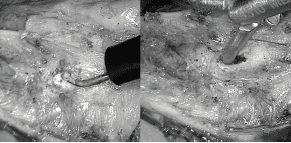

Las lesiones térmicas sobre la mucosa fueron el mecanismo más frecuente de perforación; generalmente, se presentan al intentar controlar el sangrado y requieren de una amplia sospecha 4. Deben confirmarse al sumergir el esófago en solución e insuflar aire por la sonda orogástrica o con el uso de azul de metileno 4,6. Ante la confirmación de una lesión inadvertida durante el procedimiento, se debe completar la miotomía en toda su extensión y, después de separar la mucosa, se procede a reparar la perforación (figura 1) 6.

Lesión térmica y perforación en la mucosa esofágicaFigura 1. Lesión térmica y perforación en la mucosa esofágica